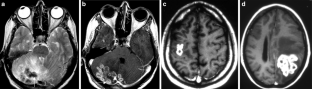

The CNS TB can be manifested (1) diffuse as tuberculous meningitis (TBM), (2) localized as tuberculoma or (3) tuberculous abscess or (4) in extradural and intradural spinal infections. Information on clinical presentation, underlying pathology and the distinguishing features is demonstrated. The TBM is further described, which may lead to cranial nerve palsy, hydrocephalus and infarction due to associated arteritis of the basal perforators. The differential diagnoses are vast and include other infections, such as bacterial, viral or fungal meningoencephalitis, malignant causes or systemic inflammation with CNS. Complicating factors of diagnosis and treatment are HIV coinfection, multi-drug resistance and TB-associated immune reconstitution inflammatory syndrome (IRIS).